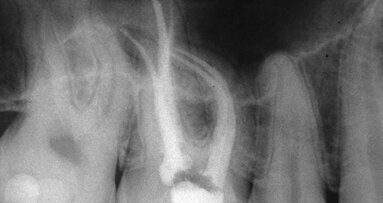

Until we get our nomenclature correct, substituting dentinal shavings for cutting, we will tend to confuse just what we want from the instruments we use. Once we understand what we want to accomplish, we immediately understand why the design and utilization of K-files defeat our goals for efficient undistorted shaping. We also understand why reamers both unrelieved (Fig. 2) and relieved with fewer more vertically oriented flutes fulfil our more accurate definition of what we want instruments to accomplish.